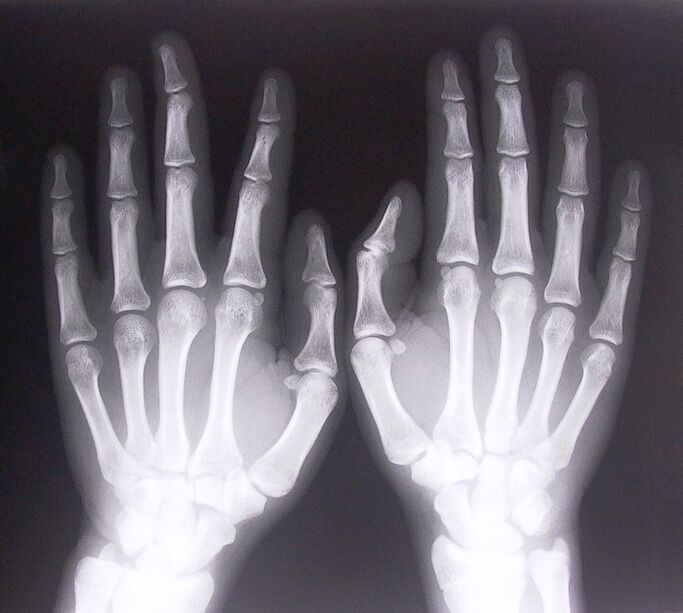

- stenosing tendonitis.To determine the cause of the disease, X-rays are needed.Typical symptoms are: pain when moving the hands and clenching the palms into circles.Additionally, a clicking sound is often heard during the extension process.

- Take X-rays.